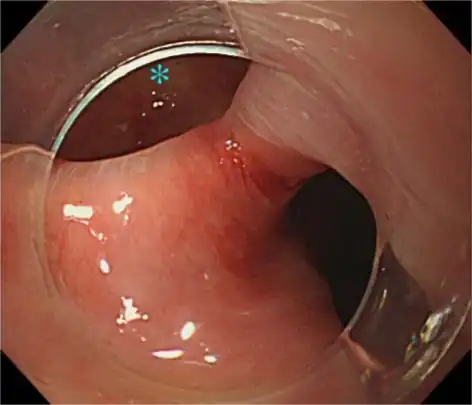

Hood-assisted upper endoscopy clarified the border of Zenker diverticulum ( and upper esophagus)